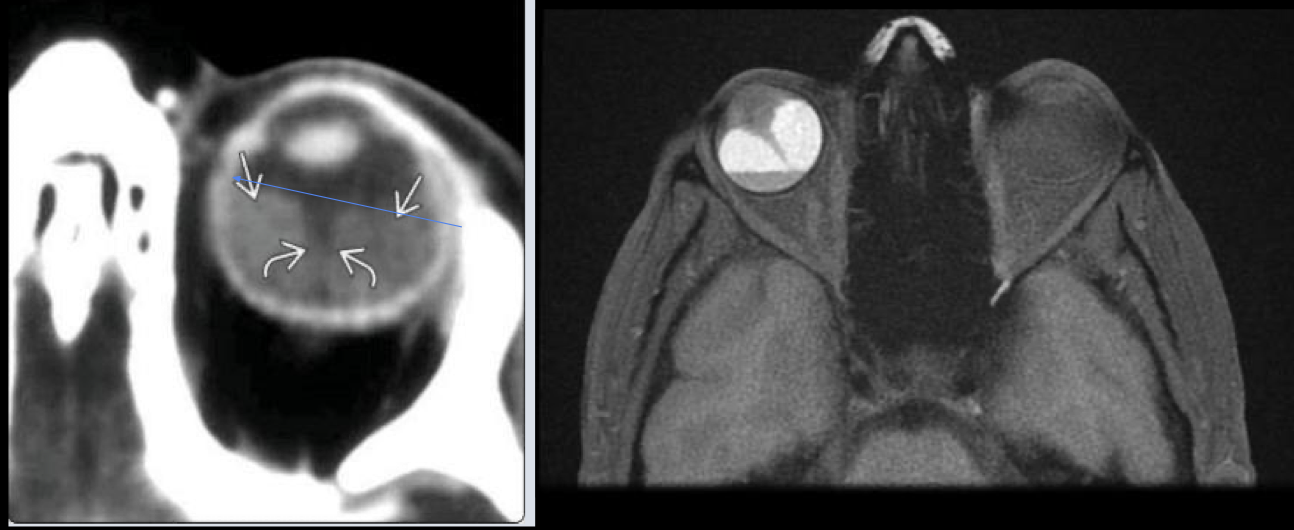

Calcificación “manchada” o punteada en globo ocular

Masa con densidad intermedia

Contraste

RB en TC